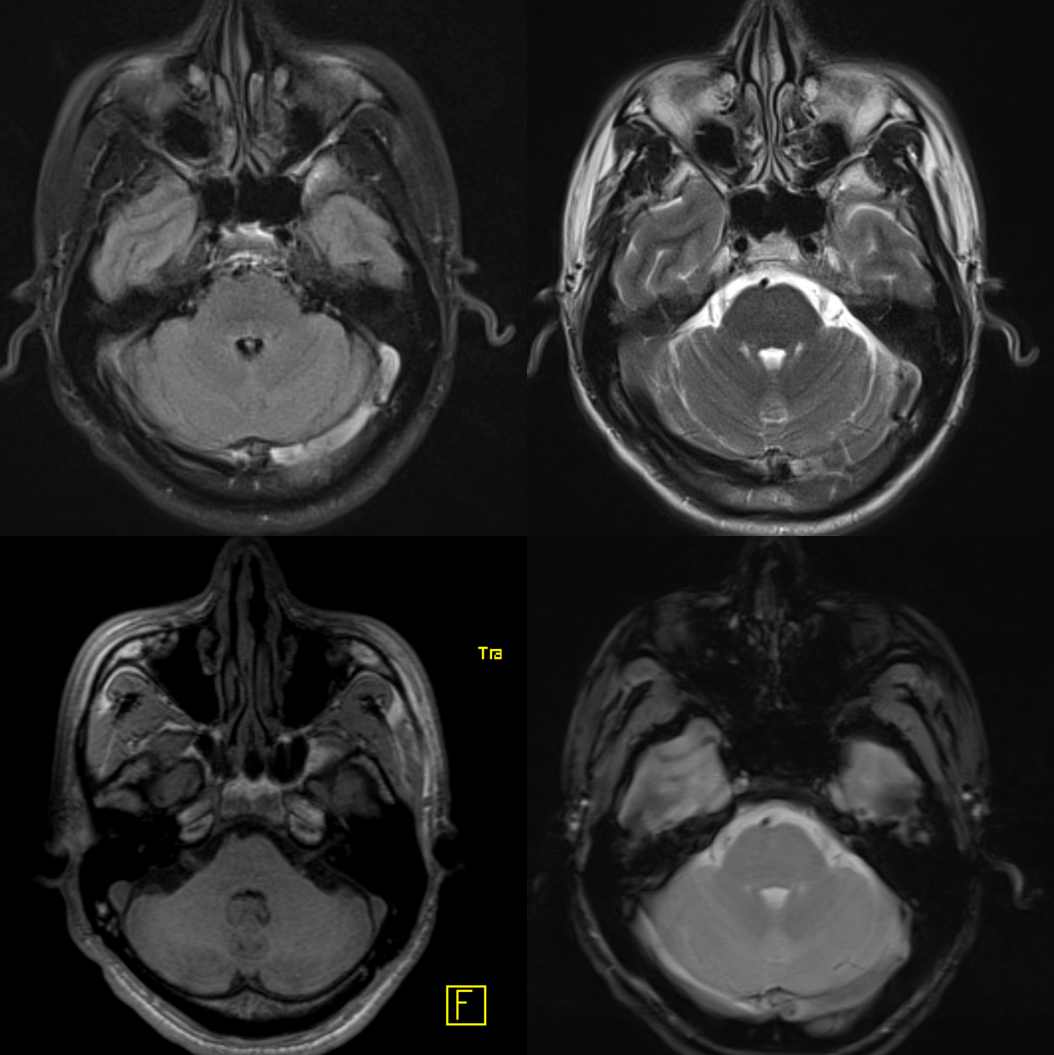

Another compensation for hypoplasia of the SSS is shift of superficial drainage into the deep venous system via the medullary veins draining into the internal cerebral veins. Courtesy Dr. Gopi Nayak. There is hypoplasia of the Superior Sagittal Sinus.

As one way of compensation for this superficial venous system deficiency, there is more venous drainage routed to the deep system. Amazing images of deep medullary/transverse venous prominence — completely nonpathologic, simply reflecting a shift of drainage equilibrium towards the deep venous system

Some arrows. Open white arrows — septal veins on the medial aspect of frontal horn. Thick white arrows — longitudinal caudate venous arcade. Black arrow — direct lateral vein, prominent because of hypoplasia of the posterior segment of the left longitudinal caudate vein. Thin white arrows are transverse/ medullary veins